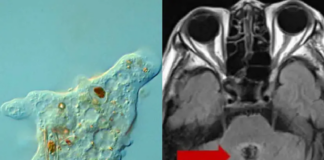

Médicos diagnostican a abuelita con cáncer cerebral; en realidad una ameba...

En China, una mujer de 77 años falleció a causa de una rara ameba devoradora de cerebros, luego de que los médicos inicialmente diagnosticaran...